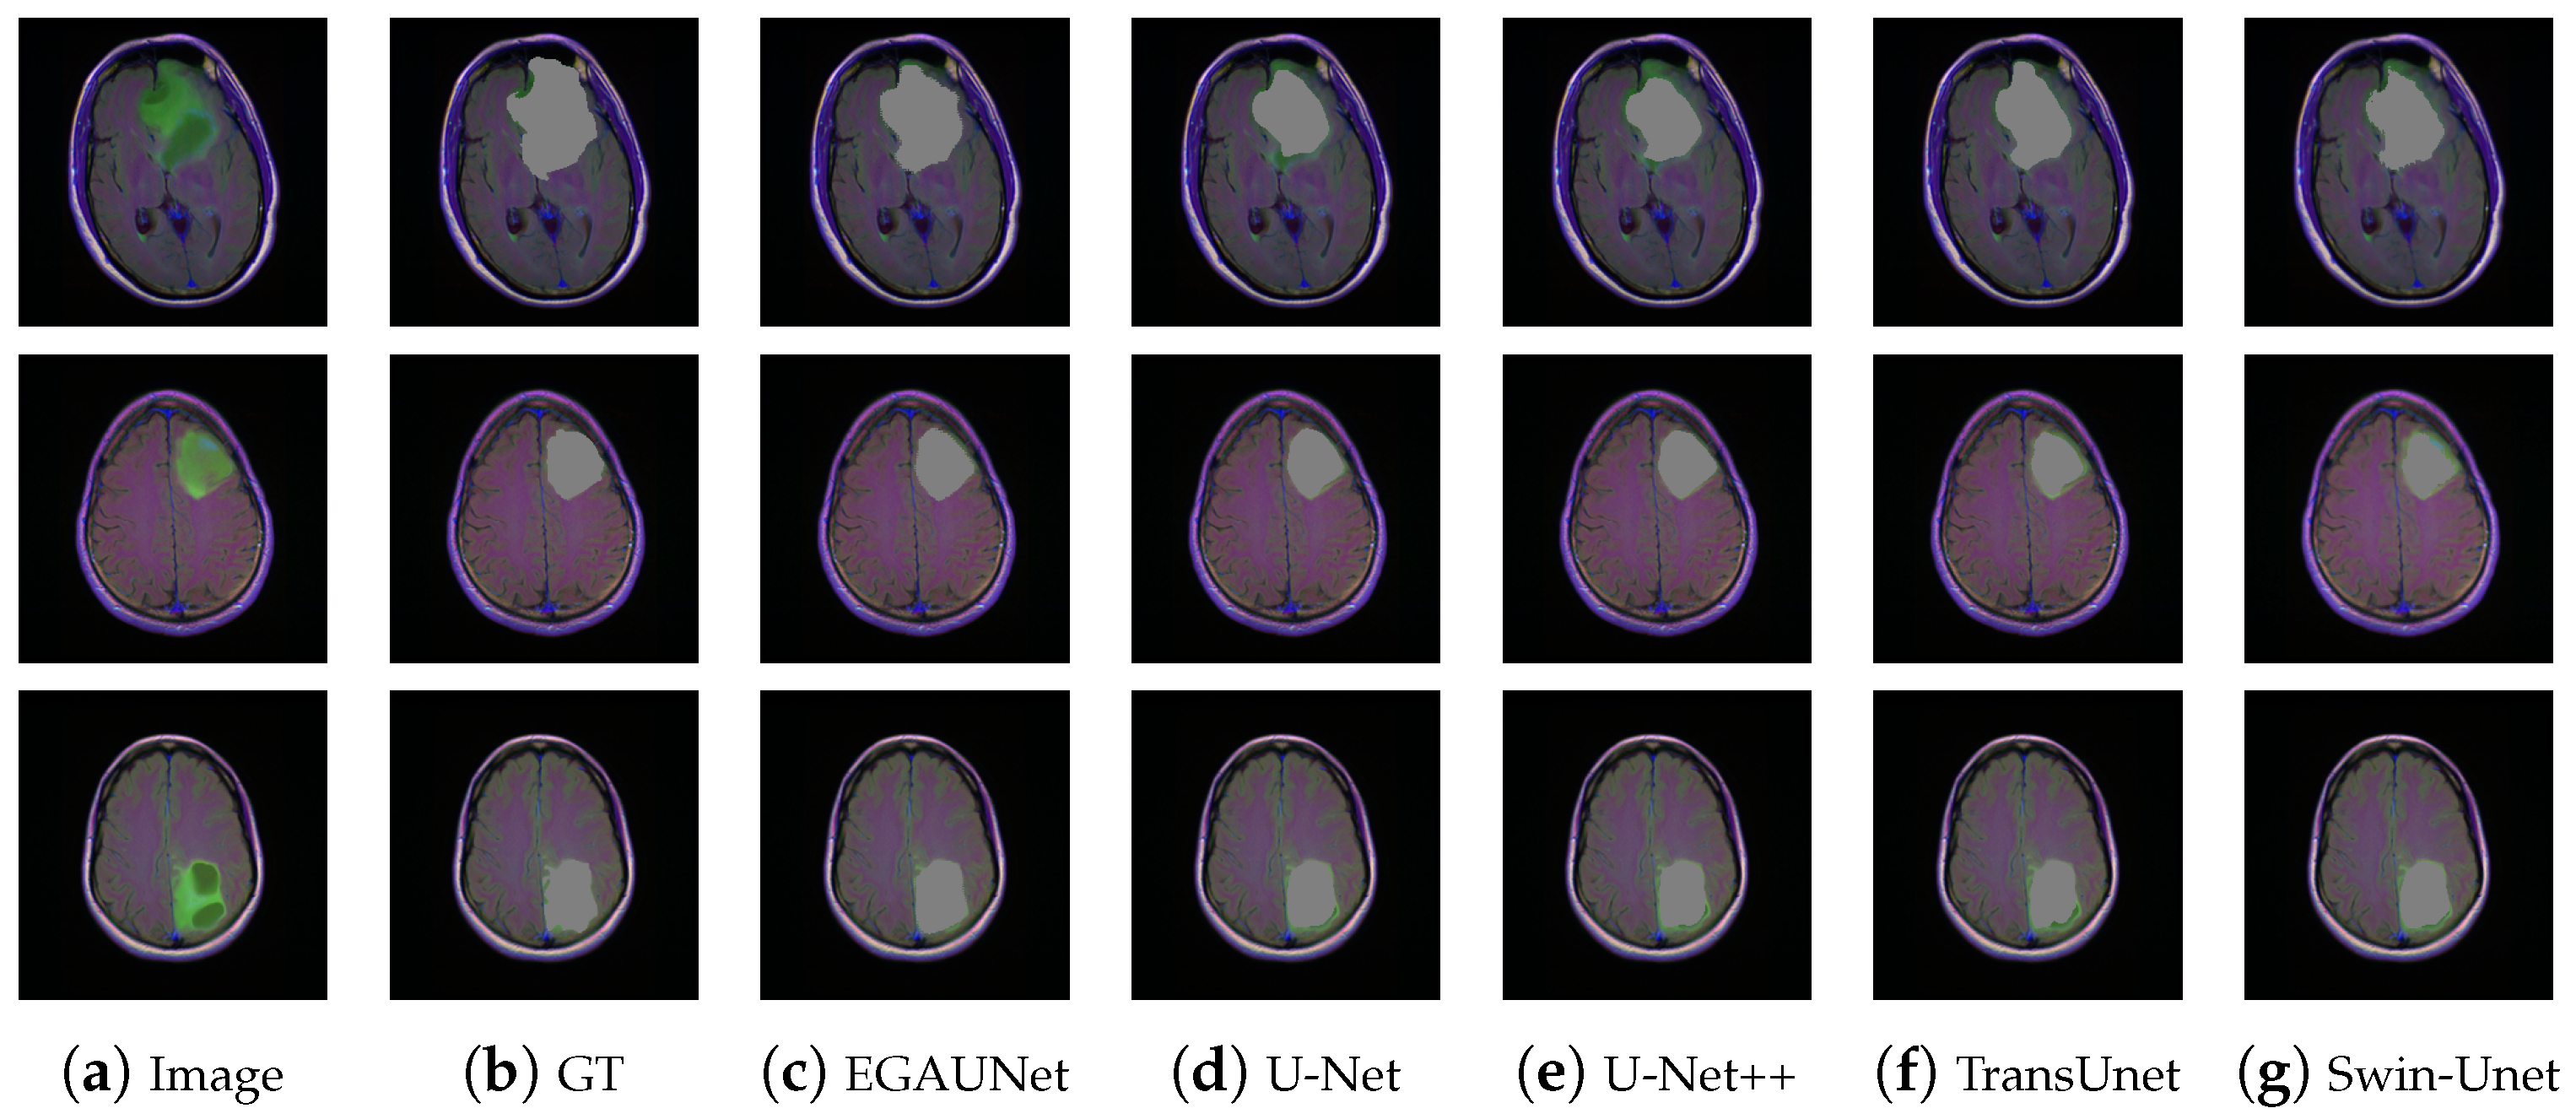

4.3.3. Brain MRI Dataset

| Methods | Accuracy/% | Jaccard/% | Dice/% | Recall/% | Precision/% |

|---|---|---|---|---|---|

| U-Net [22] | 99.1921 | 70.0793 | 73.9475 | 73.2199 | 78.4849 |

| U-Net++ [24] | 99.222 | 70.684 | 73.9475 | 73.2199 | 78.4849 |

| DeepLabV3+ [37] | 99.2099 | 70.6161 | 73.8614 | 73.9679 | 77.5365 |

| DeepLabV3 [36] | 99.2552 | 71.5492 | 74.826 | 75.2761 | 77.5441 |

| FPN [35] | 99.264 | 71.0808 | 74.5197 | 74.3894 | 78.5029 |

| PSPNet [34] | 99.2063 | 70.1365 | 72.8361 | 73.1024 | 75.1314 |

| PAN [39] | 99.2041 | 70.0225 | 72.6904 | 72.513 | 76.0798 |

| MA-Net [43] | 99.2188 | 71.0317 | 74.0247 | 74.2834 | 77.2081 |

| LinkNet [38] | 99.2272 | 70.6377 | 74.4036 | 76.3936 | 77.3731 |

| TransUnet [32] | 99.2383 | 70.8217 | 73.8083 | 73.0028 | 77.9385 |

| Swin-Unet [33] | 99.3482 | 72.0496 | 75.797 | 75.9722 | 79.0336 |

| EGAUNet | 99.3067 | 72.4873 | 75.8443 | 76.2431 | 78.7209 |